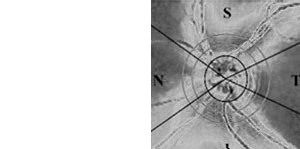

Neuroophthalmologische Diagnostik

Hilfreich ist das Gerät auch zum Nachweis, zur Quantifizierung und

zur Verlaufskontrolle bei Störungen der Pupillenmotorik von Kindern und

Erwachsenen.